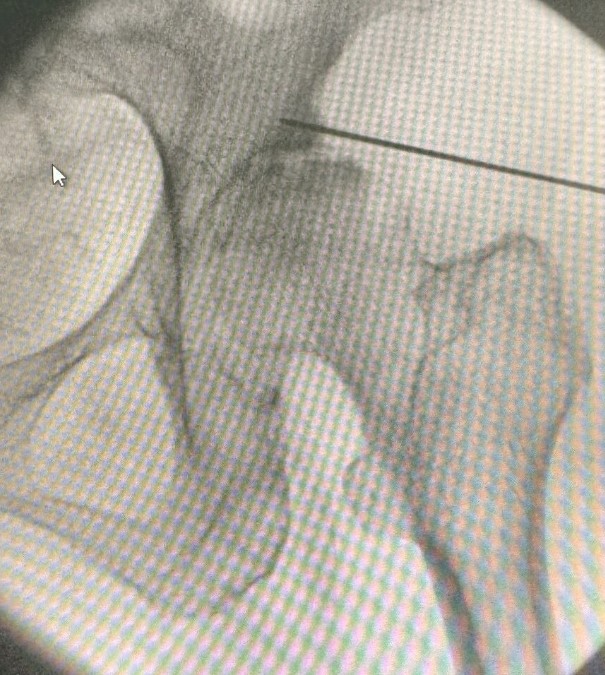

• Σε αρχικά και μέσα στάδια, η νόσος μπορεί να αντιμετωπισθεί με φαρμακοθεραπεία, εγχύσεις κορτιζόνης και υαλουρονικού στην άρθρωση υπό υπερηχογραφική ή ακτινοσκοπική καθοδήγηση  και φυσικοθεραπεία.